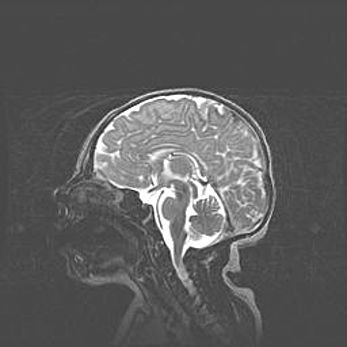

Мальформация Денди-Уокера. Киста задней черепной ямки.

Агенезия мозолистого тела.

Возраст: 2,5 месяца

Вес: 2420 г

Пол: женский

Окружность головы: 37 см

Срок гестации: 32 недели

Мальформация Денди—Уокера — редкий вид патологии ЦНС, представляющий собой врожденный порок развития каудального отдела ствола и червя мозжечка, ведущий к неполному раскрытию срединной (Мажанди) и латеральных (Лушка) апертур IV желудочка мозга. Для этогно синдрома характерна триада симптомов: гипотрофия червя мозжечка и/или полушарий мозжечка, кисты задней черепной ямки, гидроцефалия различной степени. В 70% случаев порок сочетается и с другими аномалиями головного мозга, в частности с агенезией мозолистого тела.